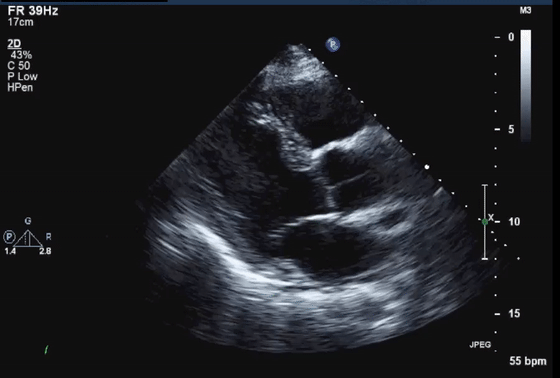

7、近场杂波

由于探头换能器本身的高振幅振荡,近场结构有时会被遮蔽,造成所谓的近场杂波。这在怀疑有心尖室血栓的病例中尤其重要(图7,视频10)。谐波成像的引入和换能器设计技术的进步已经减少了这种伪影的发生。

图7 心尖四腔视图中的近场杂波(箭头),疑似心尖血栓。(视频10)显示正常的心尖心肌动力学,杂乱回波和心肌运动之间没有关系。